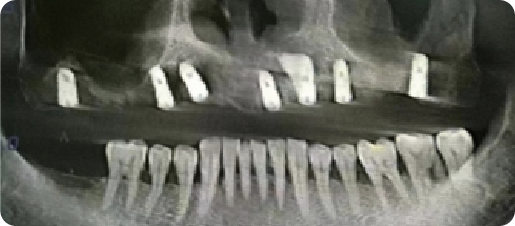

Case of Multiple Missing Teeth with Mobility of the Residual Dentition

BEFORE

VS

AFTER

Name:Mr NiuAge:64

Evaluation: Generalized tooth mobility and multiple tooth loss secondary to poor periodontal status

Treatment Plan:Two implants were placed in both the maxillary and mandibular anterior regions, each supporting two crowns, restoring a total of four teeth, a three unit fixed bridge, with a pontic for tooth #5, was supported by two implants in positions #4 and #6 in the upper left quadran.

Patient Feedback:It feels solid—I can bite with confidence, My healthy teeth were left alone, and they look so natural and feel so comfortable, it's just like having my own teeth back.